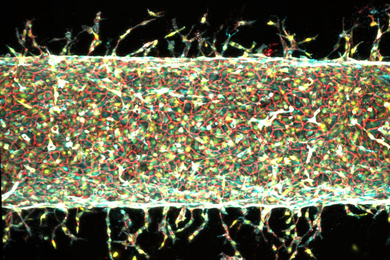

Researchers at MIT have developed injectable "mini livers" designed to temporarily take over essential liver functions, offering a potential new option for people with liver failure who are waiting for a transplant—or who aren't eligible for one at all.

Researchers at MIT are developing a new kind of sensor that detects cancer-related signals inside the bladder and emits a fluorescent light to reveal their presence. By using these nanosensors to map bladder cancer biomarkers in real time, this approach could transform how we monitor and diagnose the disease.